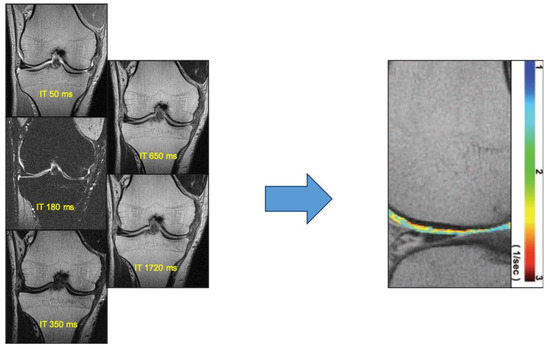

4.2. T2 Mapping